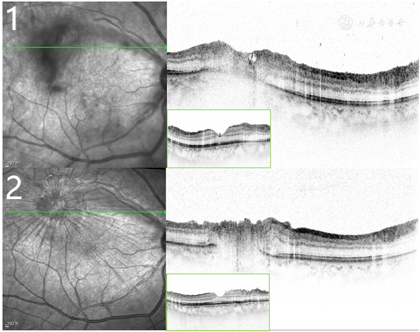

右眼裸眼视力0.5,矫正无提高;左眼裸眼视力1.0;右眼眼压18.2 mmHg,左眼眼压13.5 mmHg。双眼第一眼位正位,各方向运动无受限,右眼结膜充血,角膜KP(++),前房深、房水清,瞳孔圆,直径约3 mm,直间接对光反射存,晶体轻度混浊,玻璃体混浊,见细胞(+),眼底视盘界清,色淡红,C/D约0.3,颞上血管弓处见一黄白色绒球样病灶,位于视网膜下,邻近血管白鞘,后极部视网膜平伏;左眼结膜无充血,角膜透明,前房深、房水清,瞳孔圆,直径约3mm,直间接对光反射存在,晶体轻度混浊,玻璃体絮状混浊,眼底视盘界清,色淡红,C/D约0.3,黄斑中心凹反光未见,后极部视网膜平伏。眼底彩照示:右眼黄斑颞上方可见黄白色病灶(图1),光学相干断层扫描(optical coherence tomography,OCT)示病灶处视网膜内层结构破坏,下方脉络膜局限性增厚(图2)。荧光抗体(Fluorescent Antibody,FA)示病灶处早期呈低荧光,晚期渗漏(图3)。吲哚菁绿血管造影(indocyanine green angiography,ICGA)示病灶处始终呈低荧光(图3)。FA及ICGA晚期中周部和周边部网膜均可见广泛的点片状低荧光病灶(图3)。

临床上,获得性OT以玻璃体炎伴坏死性视网膜脉络膜炎为主,易误诊。本例患者眼底表现为黄斑颞上方黄白色绒球样病灶,需考虑与如细菌性及真菌性眼内炎、梅毒性葡萄膜炎、结核性葡萄膜炎、巨细胞病毒视网膜炎、急性视网膜坏死、眼弓蛔虫病等均可表现为坏死性视网膜脉络膜炎的疾病相鉴别,如细菌性及真菌性眼内炎起初也可表现眼底脉络膜白色病变,并迅速进展累及视网膜和玻璃体,OT进展相较而言更缓慢;梅毒性葡萄膜炎可有大片视网膜坏死,结核性葡萄膜炎可出现脉络膜视网膜疤痕,对于缺乏潜在感染的免疫学证据、缺乏特征性表现的情况,鉴别往往依赖于侵入性检测;急性视网膜坏死表现为广泛的视网膜周边白色坏死灶,而OT主要表现为局限性视网膜坏死;巨细胞病毒视网膜炎可有局限性脉络膜视网膜病变,但玻璃体炎症往往较轻,多表现为后极部视网膜坏死灶伴出血;眼弓蛔虫病也可表现为眼底白色坏死病灶,且与OT两者均常单侧发病,但眼弓蛔虫病常有典型的眼底肉芽肿性病变[7]。OT的诊断主要依据临床表现推定,但其临床表现的多样性以及与其他感染性、非感染性和肿瘤性疾病特征的重叠使得其诊断仍较为困难。OT是一种自限性疾病,部分OT即使用不适当的治疗也能恢复,由此,许多不典型的OT表现可能没有被正确诊断,且OT仍可引起部分患者严重、不可逆性视功能损害。因此,结合相关病史、影像学检查以及实验室检测确定诊断显得尤为重要[8]。首先,本例患者有明确的家养猫接触史。其次,该患者眼底的黄白色活动性病灶在OCT上呈现OT病灶典型的视网膜内层异常高反射以及视网膜全层反射紊乱(涂抹效应)[9],眼底血管造影检查也符合视网膜脉络膜炎的表现。此外,随着实验室检测技术的进步,通过检测眼内液和血清中弓形虫IgG与总IgG,计算出Goldmann-Witmer系数(goldmann-witmer coeifficient,GWC)已被认为是确诊OT诊断的金标准[10]。GWC>4可确诊OT,2~4提示OT可能。联合分析房水和血清的抗弓形体抗体水平和寄生DNA可以在90%诊断特异性的基础上,实现60%~70%的诊断敏感性[11]。本病例患者眼内液弓形虫IgG抗体56.74 IU/ml,血清总IgG 4680 IU/ml,弓形虫GWC>4,达到临床确诊标准。